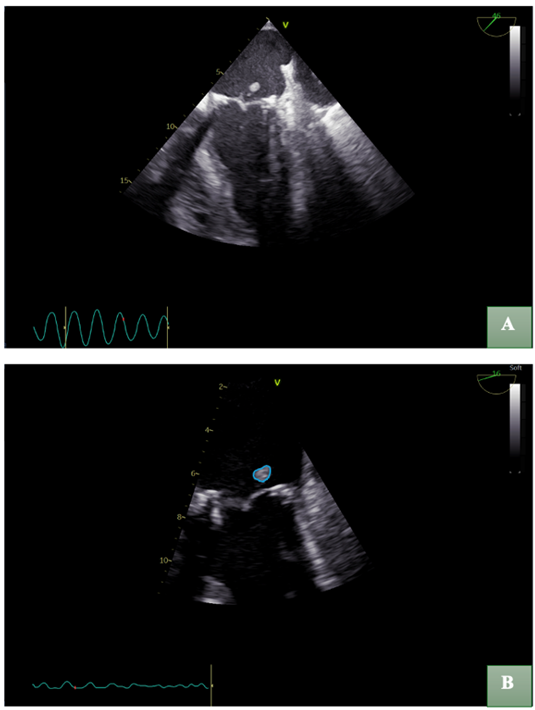

Follow-up TOE demonstrated a marked reduction in the dimensions of the vegetation (Figure 6), as well as a decrease in the mean transvalvular pressure gradient to 5 mmHg. Additionally, 7-days after admission blood cultures became negative. Despite these findings, the clinical status of the patient continued to deteriorate. Given the absence of conclusive evidence regarding the efficacy and optimal duration of conservative management, the patient was transferred to a cardiothoracic center for possible surgical intervention.

Figure 6: Follow-up transesophageal echocardiography (TOE) demonstrated a substantial reduction in vegetation size. (A) Distant view; (B) Zoomed-in view, illustrating the residual vegetation in a blue outline.